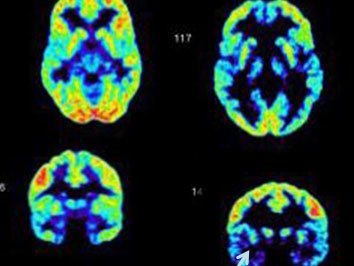

图源:zh.wikipedia.org

左边为正常人的(法隆教授的儿子),右边是罪犯/像罪犯一样的(法隆教授自己的)